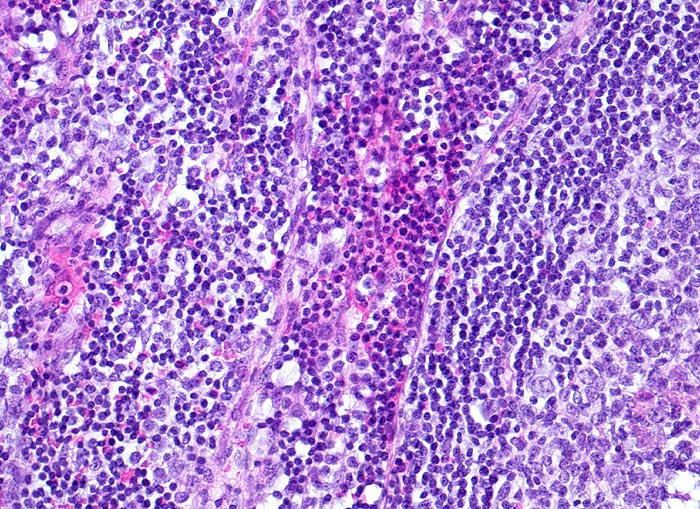

Morphologische Merkmale:

• Girlandenförmige basophile Nekrosezonen durchsetzt von neutrophilen Granulozyten (abszedierende Entzündung).

• Demarkierung der Abszesse durch palisadenförmig angeordnete epitheloide Histiozyten (heller Randwall um die Abszesse).

• Vereinzelt mehrkernige Riesenzellen im histiozytären Randwall.